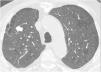

Langerhans cell histiocytosis (LCH)LCH is a rare tobacco-related interstitial lung disease diagnosed in young adults with a current or previous history of smoking. Components of tobacco smoke are thought to activate pulmonary Langerhans cells, which, along with other inflammatory cells, accumulate to form peribronchial infiltrates and granulomas that result in stellate nodules. These nodules may show cavities that correspond to bronchiolar dilatation. In the most advanced stages, peribronchial fibrosis pulls and dilates the contiguous air spaces.14 The most common symptoms are dyspnoea and cough, but there are often no respiratory symptoms. Some patients start with pneumothorax (15%), and a small percentage have systemic symptoms, pain secondary to bone involvement, cutaneous eruptions, or diabetes insipidus. Chest radiographs may reveal upper lobe nodules in the initial phases, and later reticular and cystic abnormalities, with preserved or increased lung volumes. On CT in the initial phases, peribronchiolar centrilobular nodules predominate, measuring 1−5mm, which are poorly defined or irregular, with bilateral and symmetrical distribution, predominantly in the upper and middle lung fields, with the costophrenic angles and the internal part of the middle lobe and the lingula preserved. As the disease progresses, cavitated nodules appear (Fig. 7) with thick walls and, later on, thin-walled cysts of different sizes, generally less than 1cm. However, they may coalesce in advanced stages, and large cysts with irregular or atypical (lobulated, branched, etc.) morphology are seen. (Fig. 8) Both pathologically and on CT, there is temporal heterogeneity, and cavitated nodules may coexist with thick- and thin-walled cysts.2,5,6,12 The hypothesised mechanism of cyst formation is dilatation of the bronchioles secondary to chronic inflammation with destruction of their walls.15 In the more advanced stages there is fibrotic scarring and peribronchiolar paracicatricial emphysema. The disease may return spontaneously or after smoking cessation in 25% of patients, stabilise in 50%, or progress to diffuse destructive cystic disease in 25% with respiratory failure, even after smoking cessation. Pulmonary hypertension is a complication associated with higher mortality and is usually more serious than that related to other causes, such as emphysema or pulmonary fibrosis.31 Its prevalence is high, around 40% in a recent series,32 so screening with echocardiography is indicated. In patients with long-standing disease and significant cystic involvement of the lungs, mimicking extensive emphysema, the existence of signs of pulmonary hypertension may guide us towards diagnosing LCH. It is not possible to determine with CT the subgroup of patients with LCH that will progress, so follow-up with respiratory function tests is important. Lung transplantation is an option in cases of advanced disease.

Langerhans cell histiocytosis. (A) The HRCT image centred on the upper lobes shows multiple subcentimetre nodules with irregular contours, some cavitated (white arrows) and also air-filled cystic images (black arrow). (B) The image reconstruction in the coronal plane highlights the predominant distribution in the upper lung fields, with preservation of the lung bases.